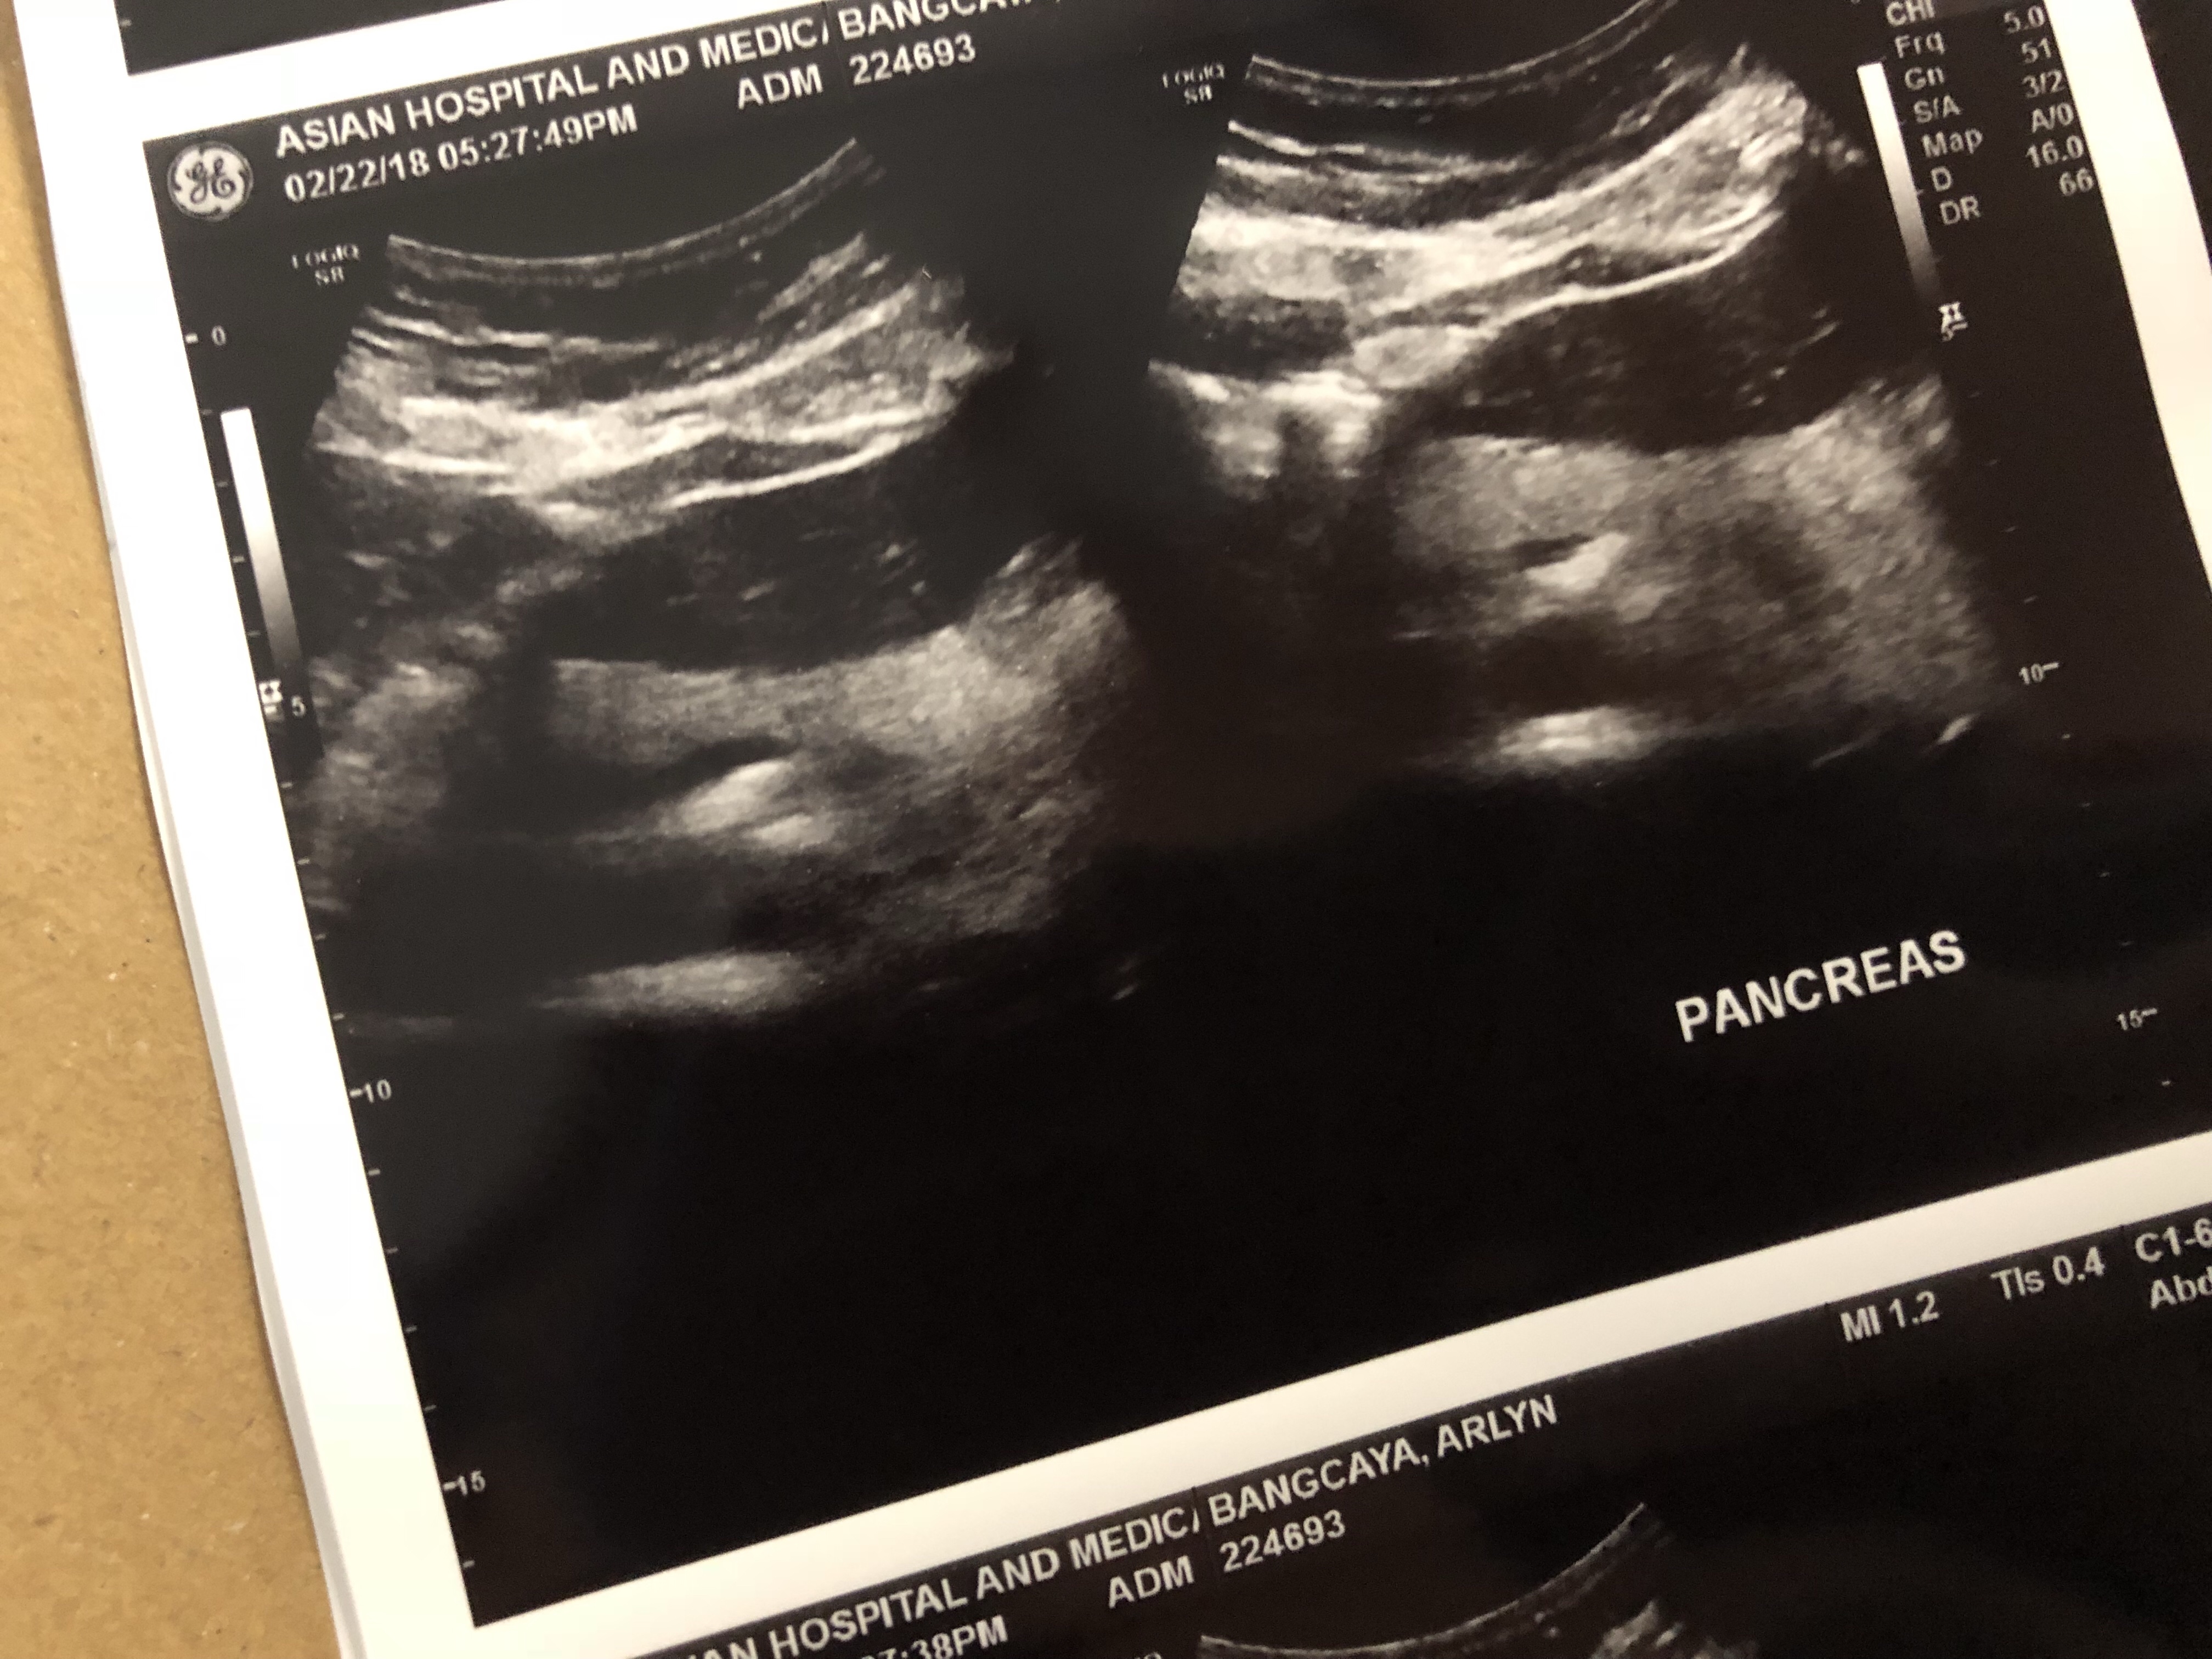

Here’s how a normal and healthy Pancreas of mine looks like if you are interested 🙂